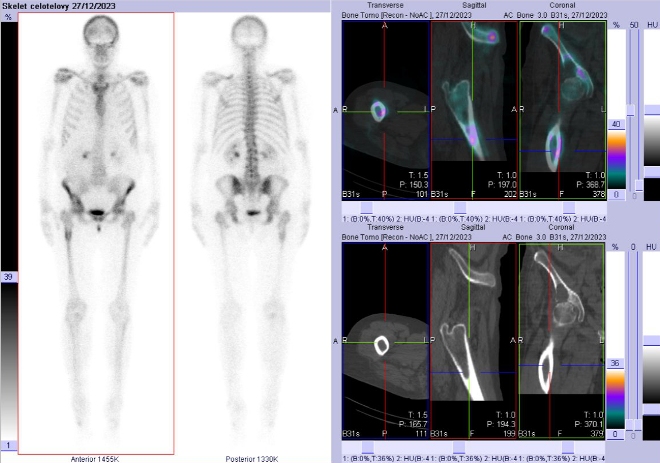

Celotělové scintigramy a SPECT/CT pánve, bederní páteře, kyčelních kloubů a proximální části stehenních kostí jsme provedli po podání 600 MBq

99mTc-oxidronátu (přípravek TechneScan HDP firmy Curium Netherlands B. V.) na hybridní tomografické scintilační kameře Symbia Intevo firmy Siemens

(obr. 6-10).

/ Obr. č. 6: Celotělová scintigrafie a SPECT/CT pánve, kyčlí a proximální části stehenních kostí.